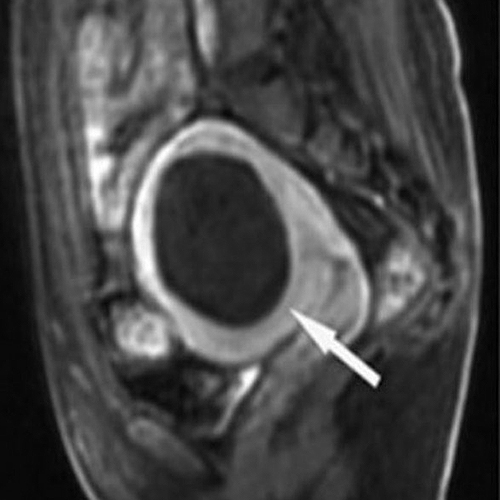

고해상도 초음파를 통해 병변의 위치와 깊이를 실시간으로 파악합니다.

질을 통해 접근하므로 복부 흉터 없이 얇은 바늘 형태의 전극을 삽입합니다.

주변 장기 손상을 방지하기 위해 병변의 80~90%만 정밀하게 타격하여 안전하게 괴사를 유도합니다.